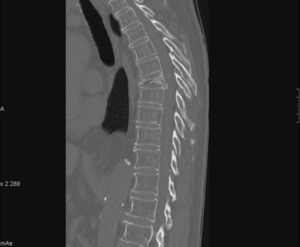

HALLAZGOS RADIOLÓGICOS